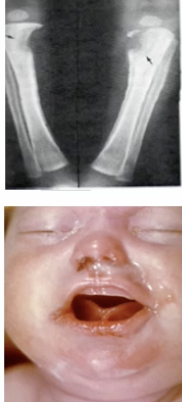

Treponema Pallidum - Gram negative spirochete which causes syphillis. Grown in special medium, slow, low oxygen conditions. Treated with penicillin

Treponema Pallidum - Gram negative spirochete which causes syphillis. Grown in special medium, slow, low oxygen conditions. Treated with penicillin (Rash of the palms and soles = Syphilis!!!!)